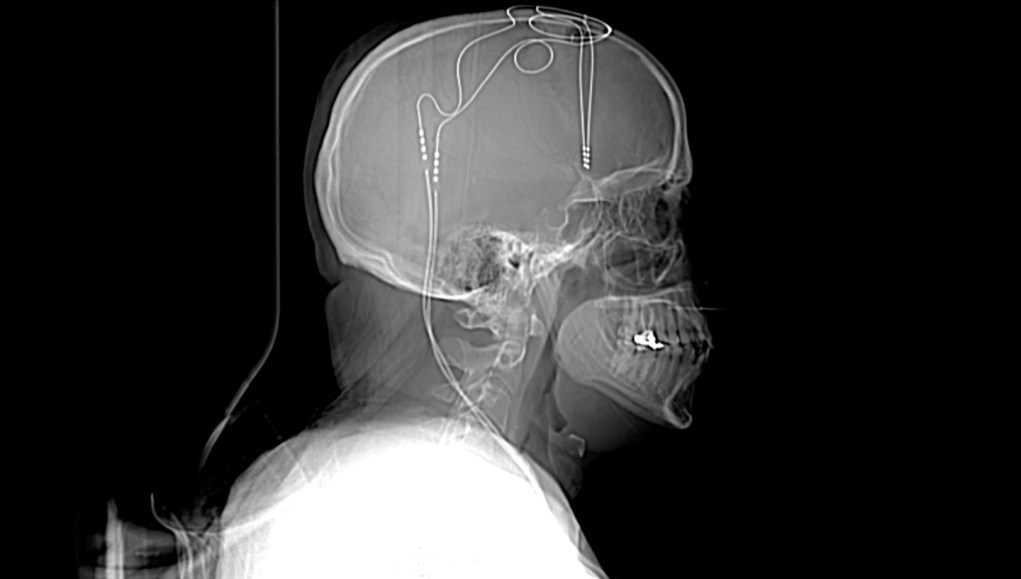

This is an X-ray of Jon Nelson, a man who volunteered for an experimental depression treatment. The image shows two thin wires of electrodes that were implanted in his brain.

THE NASH FAMILY CENTER FOR ADVANCED CIRCUIT THERAPEUTICS, ICAHN SCHOOL OF MEDICINE AT MOUNT SINAI